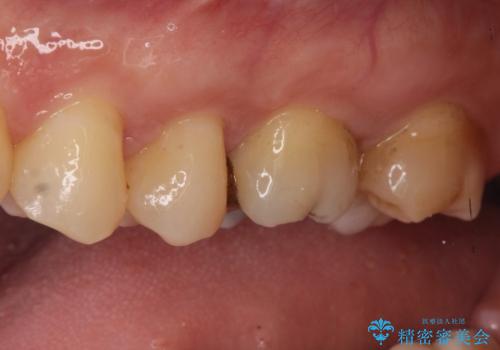

- 矯正終了後にメタルフリーの治療を希望された患者様です。

セラミックインレーにて修復治療を行なっております。

セラミックインレーのセット時にはラバーダムを用い防湿に気をつけて処置をしております。